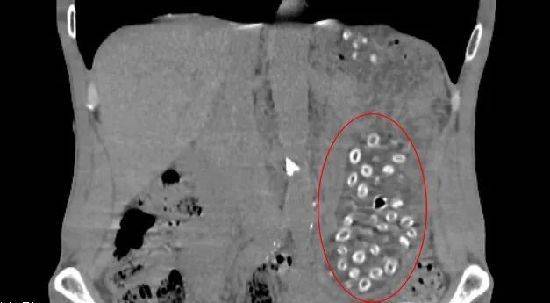

經(jīng)CT檢查后發(fā)現(xiàn)胃潴留,胃內(nèi)可見大量顆粒狀物體,密密麻麻,詢問得知王大伯近期大量食用楊梅且不吐核,以下影像中呈現(xiàn)的就是沒有消化的楊梅核。

入院后,消化內(nèi)鏡室醫(yī)生在胃鏡下實施“異物取出術(shù)”,通過異物網(wǎng)籃來回?fù)屏?00多次,取出100多顆楊梅核,目測胃里還有幾十顆。幸好發(fā)現(xiàn)的及時,不然后果不堪設(shè)想。